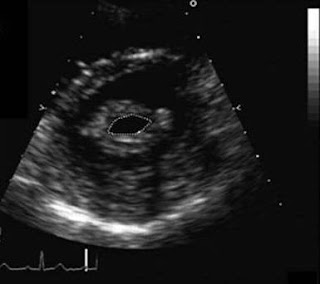

Cardiology Blog: Cardiology Case Scenario - Mitral Stenosis

Cardiology Blog: Cardiology Case Scenario - Mitral Stenosis jitesharora.blogspot.com

stenosis mitral case cardiology echo reveals patient isolated 2d